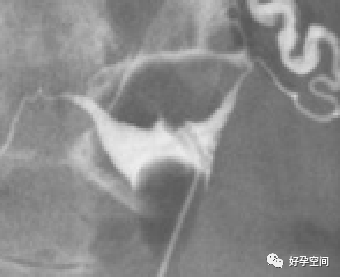

4、正常宫颈管及变异:子宫颈管的变异很大,子宫颈管的形状分为(a) 圆柱形、(b)漏斗形、(c) 球形、(d) 梨形、(e)纺锤形五型。

圆柱形宫颈

漏斗形宫颈

球形宫颈

梨形宫颈

纺锤形宫颈